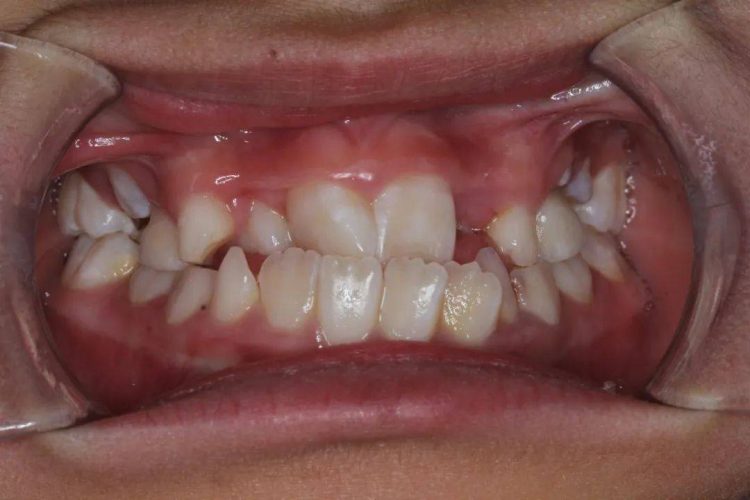

Crowding: teeth arranged too densely, resulting in overlapping or misalignment of some teeth.

Anterior protrusion : The front teeth protrude forward, commonly known as “protruding teeth”.

Deep overbite: Excessive coverage of the lower front teeth by the upper front teeth can lead to abnormal bite relationships.